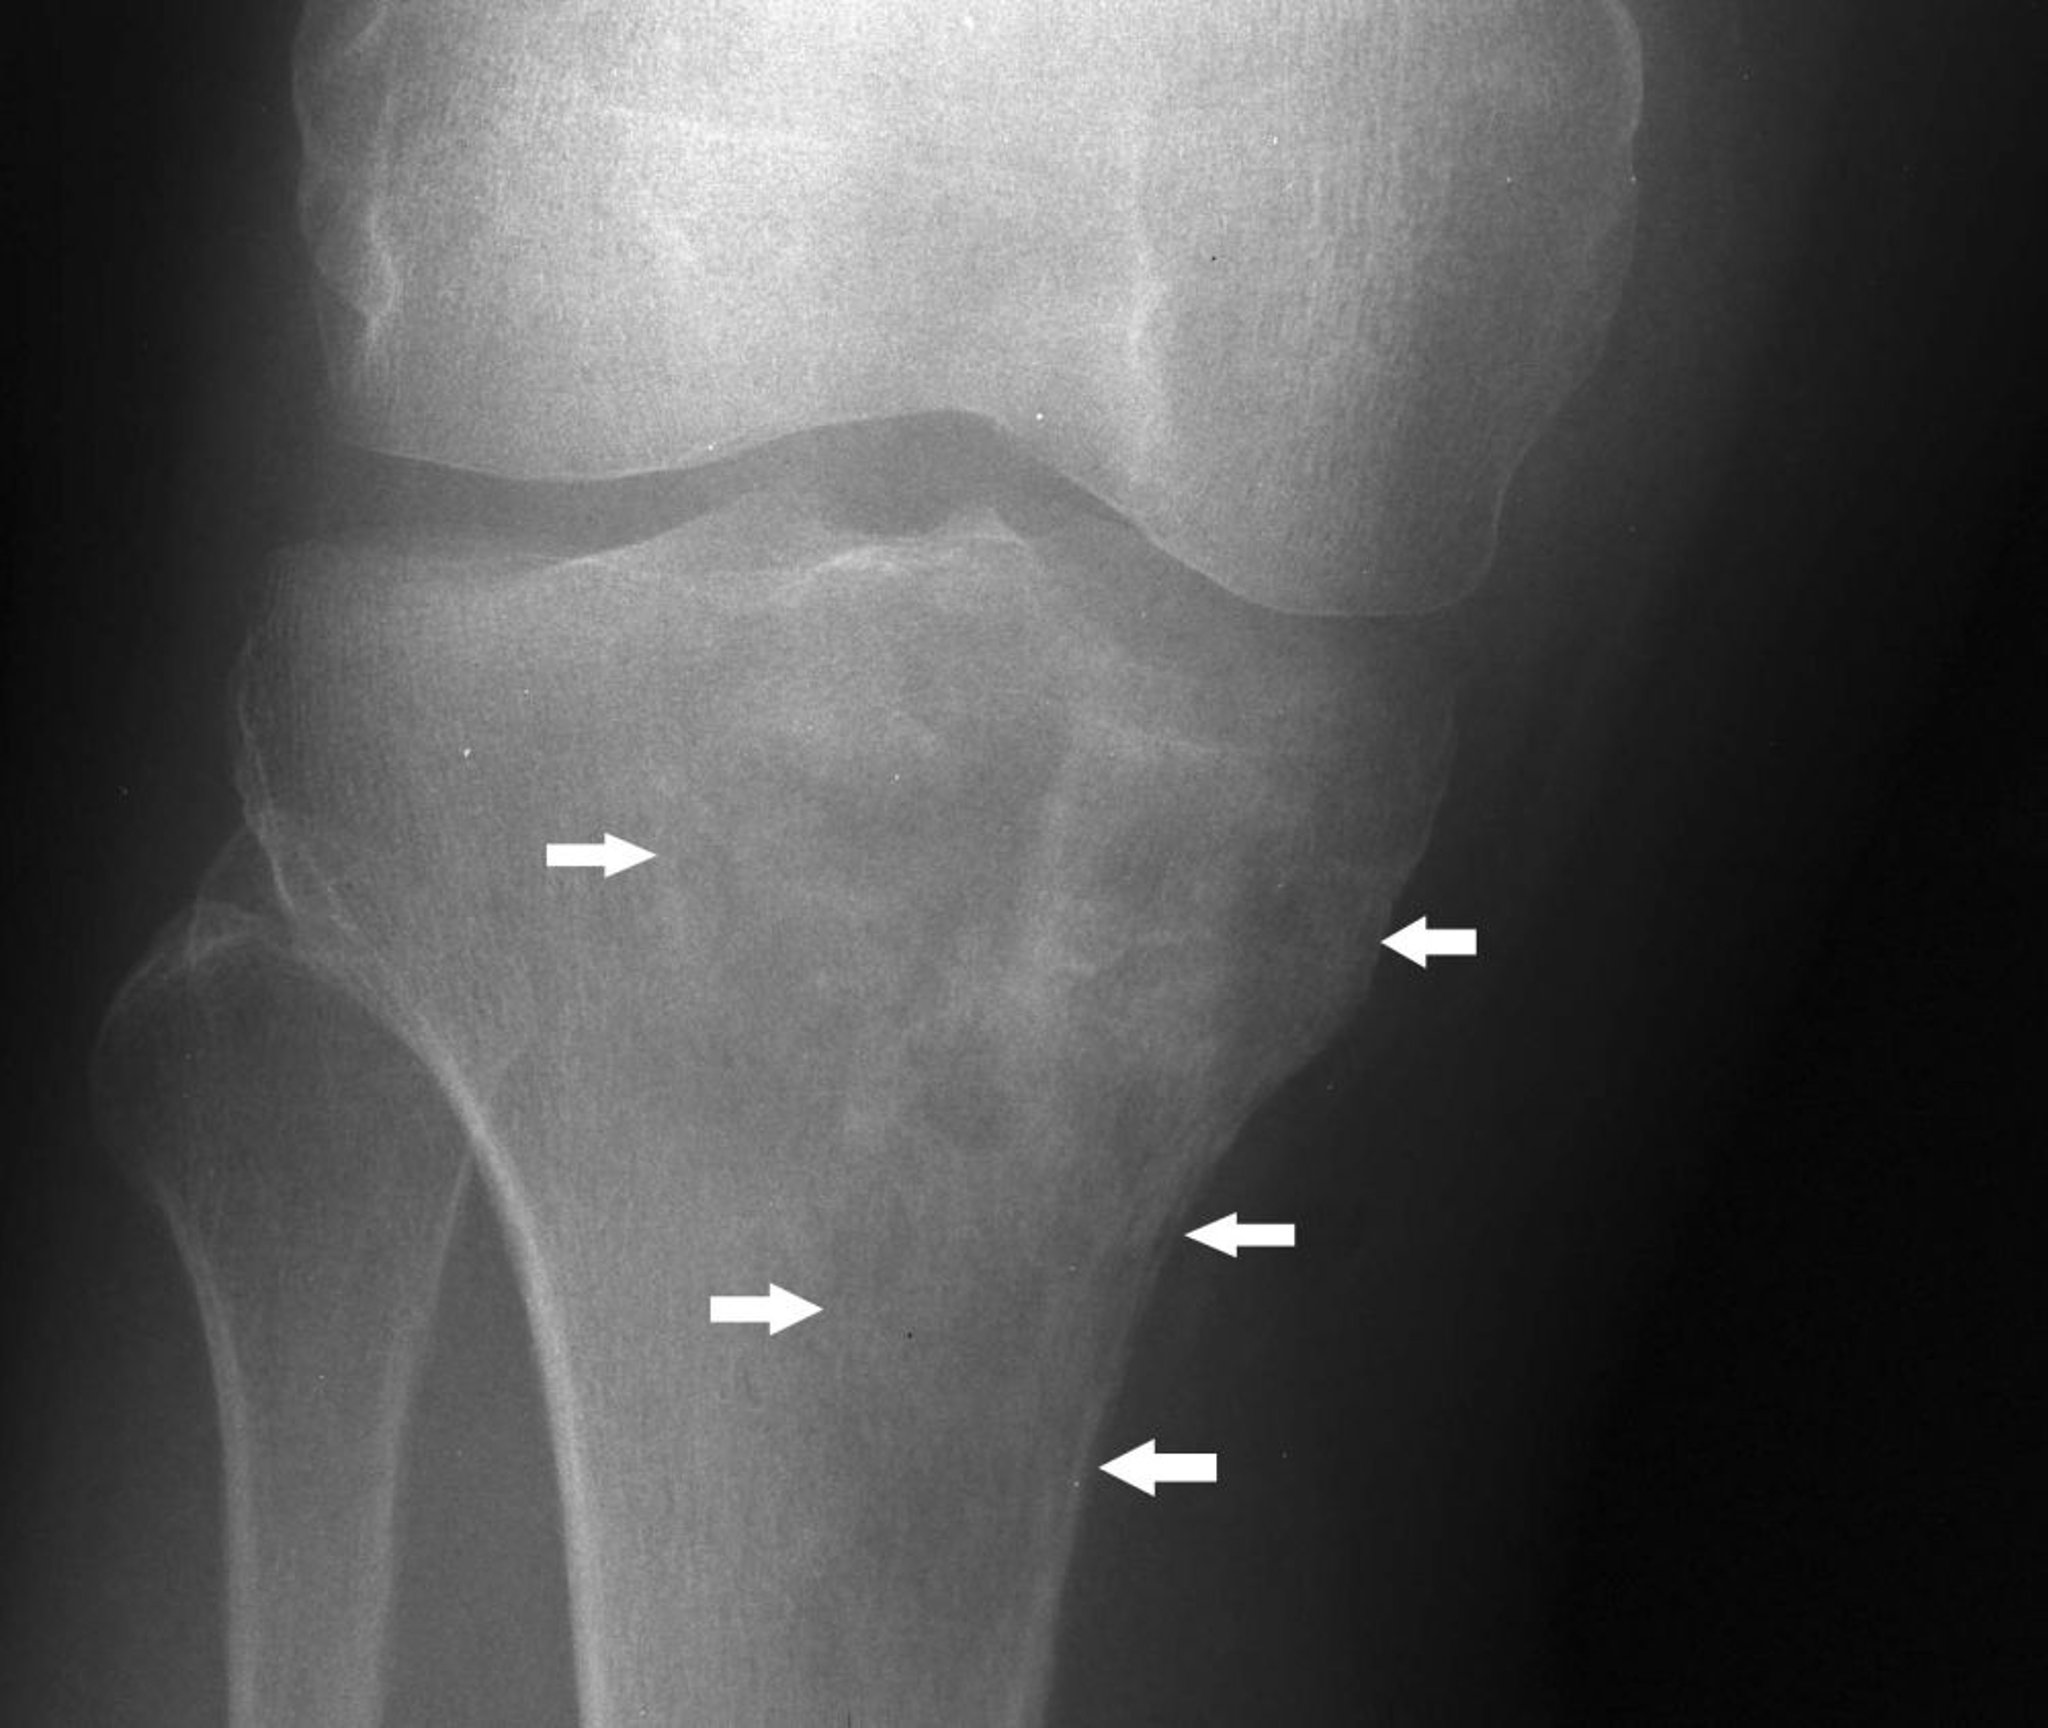

Esta radiografía de rodilla muestra un linfoma en la tibia proximal con una apariencia mixta lítica y esclerótica debajo del cóndilo tibial medial (flechas).

Image courtesy of Michael J. Joyce, MD, and Hakan Ilaslan, MD.